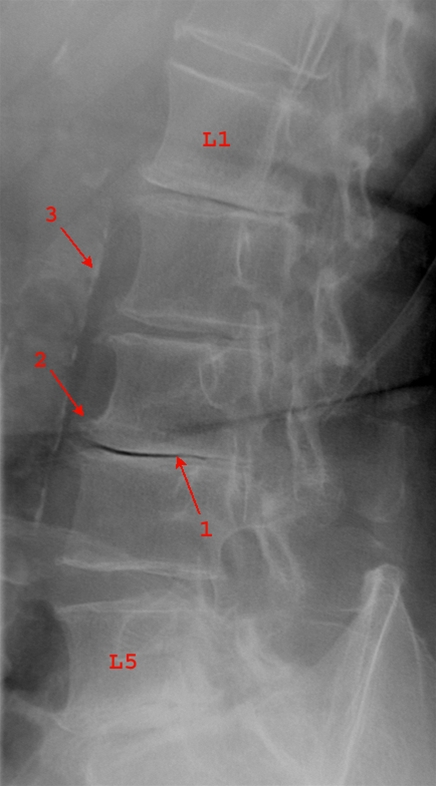

Reduceret diskushøjde i lumbale niveauer

1. Lav diskusskive mellem L3/L4

2. Lette til moderate randudbygninger